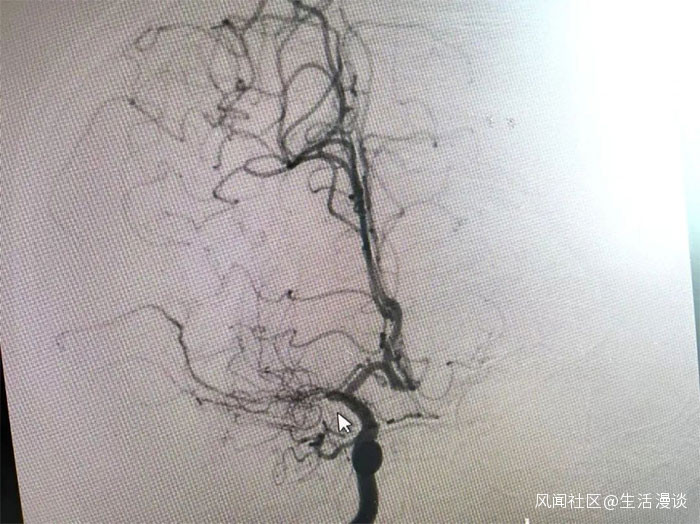

在檢查中發現,周先生右側大腦中動脈M1段閉塞,可見煙霧狀異常血管網生成;左側大腦中動脈M1段重度狹窄(約70%)。符合煙霧病的典型影像學特徵。

▲ 檢查發現煙霧狀異常血管網

▲右側大腦中動脈M1段閉塞,左側重度狹窄